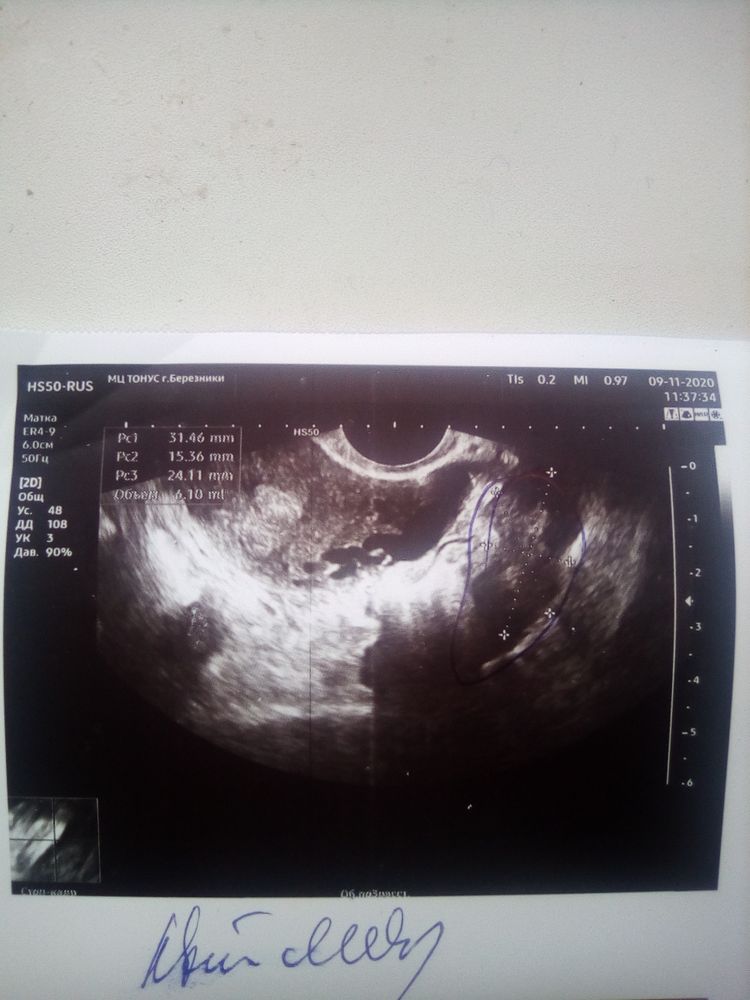

Сдайте ХГЧ в динамике 2 раза, через 48 часов. Если будет расти, и больше 1500, то идите снова на УЗИ - уже увидят ПЯ. А вообще, странно, что не увидели желтое тело, и эндометрий 7 мм - это "небеременный" эндометрий. А когда у Вас последние месячные были?

Вам нужно сдать хгч 2 раза через день, убедится, растёт ли он как при беременности. Зарегистрированы случаи когда после О не формируется ЖТ, а женщина беременеют, в таких случаях назначают большие дозы прогика дабы расла матка. Вполне может ваша миома оказаться плодным яйцом. Фото у вас есть?

Размер матки не беременный совсем.

тест на берменность ХГЧ 3000 на УЗИ нет беременности